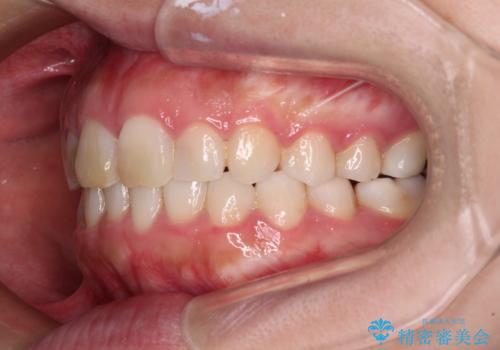

- ワイヤーではない矯正治療があると聞いたとのことで来院された患者様です。

長年前歯のデコボコを気にしていたもののワイヤー矯正に抵抗があり躊躇していたそうですが、インビザラインなら治療してみたいとのことで相談にいらっしゃいました。

インビザライン適用の歯列であったため、歯と歯の間を削るIPRを用いて改善することとしました。

お仕事柄、長時間のマウスピース装着が苦ではなかったので、歯列はすぐに整いましたが、ゆっくりとした交換頻度であったので、2年ほどの治療期間を要しました。